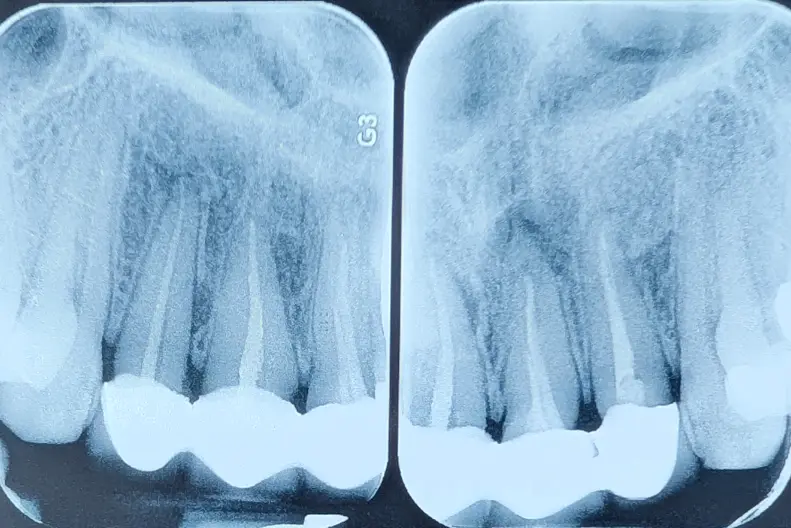

ارزیابی دندان زیر روکش اسپلینت شده

در بیمارانی که روکش قبلی آنها می‌بایست خارج شود، تا زمانی که روکش برداشته نشود، وضعیت واقعی دندان—حجم تاج، پوسیدگی، ترک—قطعاً معلوم نیست. این یک قانون همیشگی‌ست.

اما وقتی چند دندان به‌صورت اسپلینت کنار هم قرار گرفته‌اند، این عدم‌قطعیت چند برابر می‌شود؛ چون افرادی که دندان‌ها را بی‌دلیل اسپلینت می‌کنند، خیلی احتمال دارد که دندان‌های Hopless را هم برای نگه‌داشتن، به دندان‌های سالم اسپلینت کنند و ظاهر کار گول‌زننده می‌شود.

بیمار برای تعویض چهار روکش متصل به هم مراجعه کرده بود.

ارزیابی دندان همیشه پس از برداشتن روکش است—اما در روکش‌های اسپلینت، باید آمادگی بیشتری برای هر سناریویی داشت.